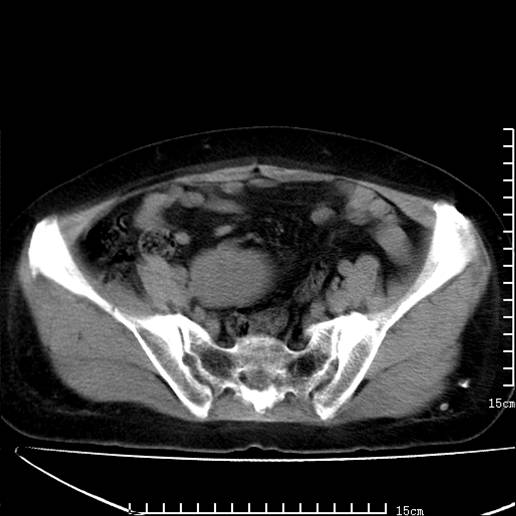

以下是引用pujunzhi在2008-5-30 15:31:00的发言:[br]异位肾—盆腔肾。当看到肾窝无肾脏时,要想到孤立肾和异位肾,异位肾最常见是盆腔肾,偶见胸腔,易误认为肺占位,只要想到就不会漏诊。建议增强扫描。